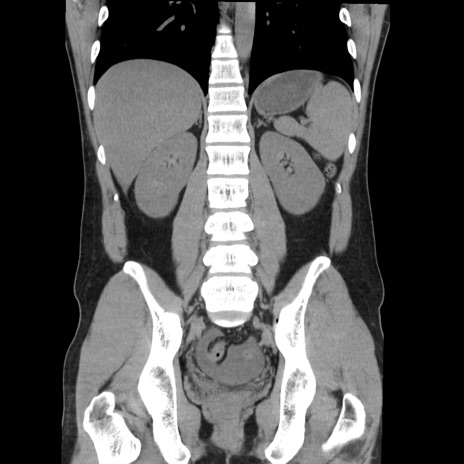

症例36(冠状断像)

【症例】20歳代 男性

【主訴】心窩部痛

【現病歴】今朝より上腹部痛あり。一旦軽快していたが再度出現したため救急要請。昨日夕に白身の魚を含む刺身を食べた。

【身体所見】BP 136/89mmHg、HR 74/min、BT 37.0℃、腹部:膨満、軟、心窩部に圧痛あり。反跳痛なし、筋性防御なし、腸雑音やや亢進あり。

【データ】WBC 17700、CRP 0.48